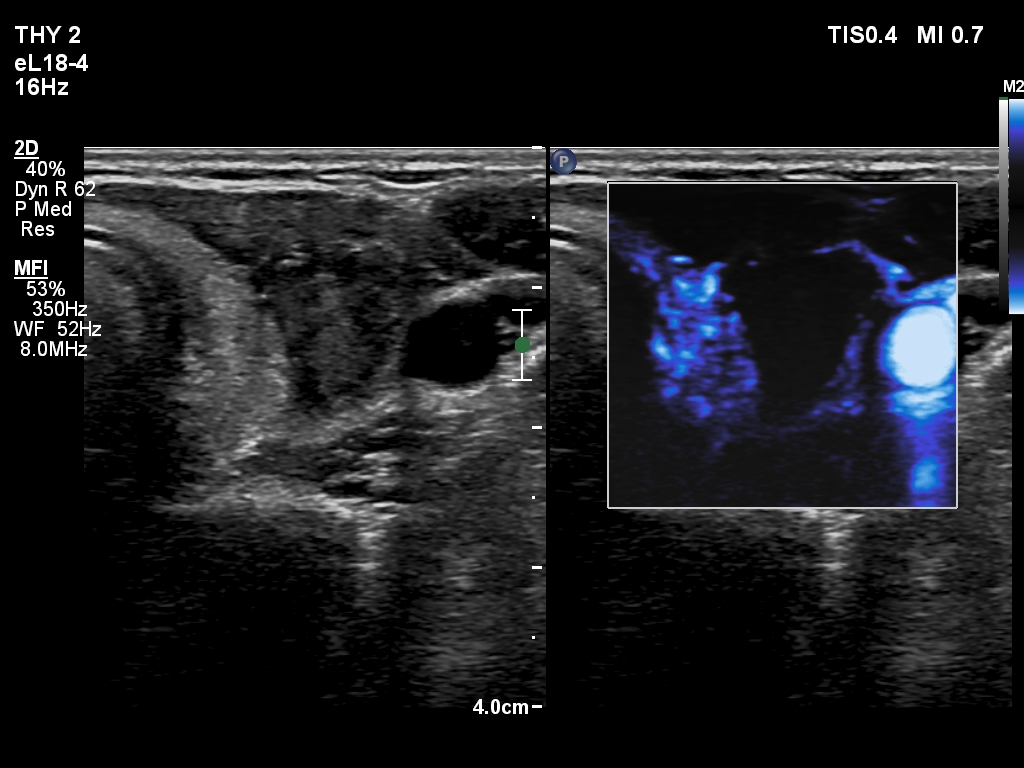

The composition of the nodule - case 2176

Two months after the sclerotherapy (ultrasonographic picture 4)

Left lobe, transverse scan, microflow imaging. There are only two vessels within the nodule, these are in the medial part.